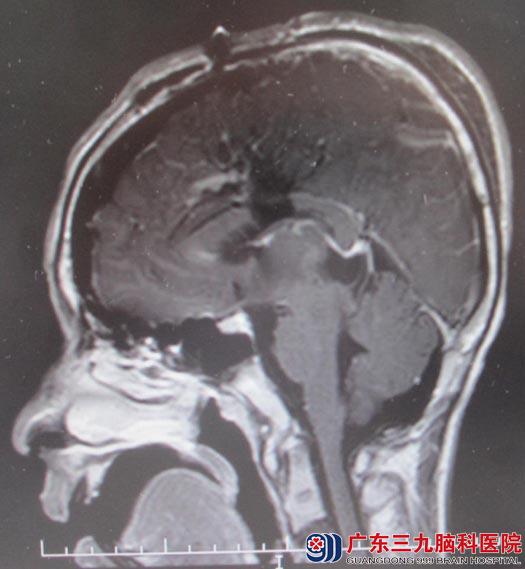

小杨一个多月前出现头痛,以额部明显,阵发性钝痛,未予重视;3天前,头痛较前明显加重,并出现呕吐,视力下降,视物重影,当地医院行头颅CT检查示“松果体区占位,直径约2.5cm,伴梗阻性脑积水”。入住广东三九脑科医院综合神经外科,头颅MR证实了当地医院的检查结果。

2月11日急诊行“左侧脑室外引流术”,2月12日转入肿瘤综合治疗中心行术前放疗, 2月16日行“经纵裂胼胝体穹窿间入路松果体区肿瘤切除术”,术程顺利,术中肿瘤全切,复查头颅MR未见肿瘤残留。术后仍有视物重影,但无明显头痛、头晕,无脑积水相关症状,肢体活动良好。病理结果提示为混合性生殖细胞瘤(精原细胞瘤与畸胎瘤混合)。